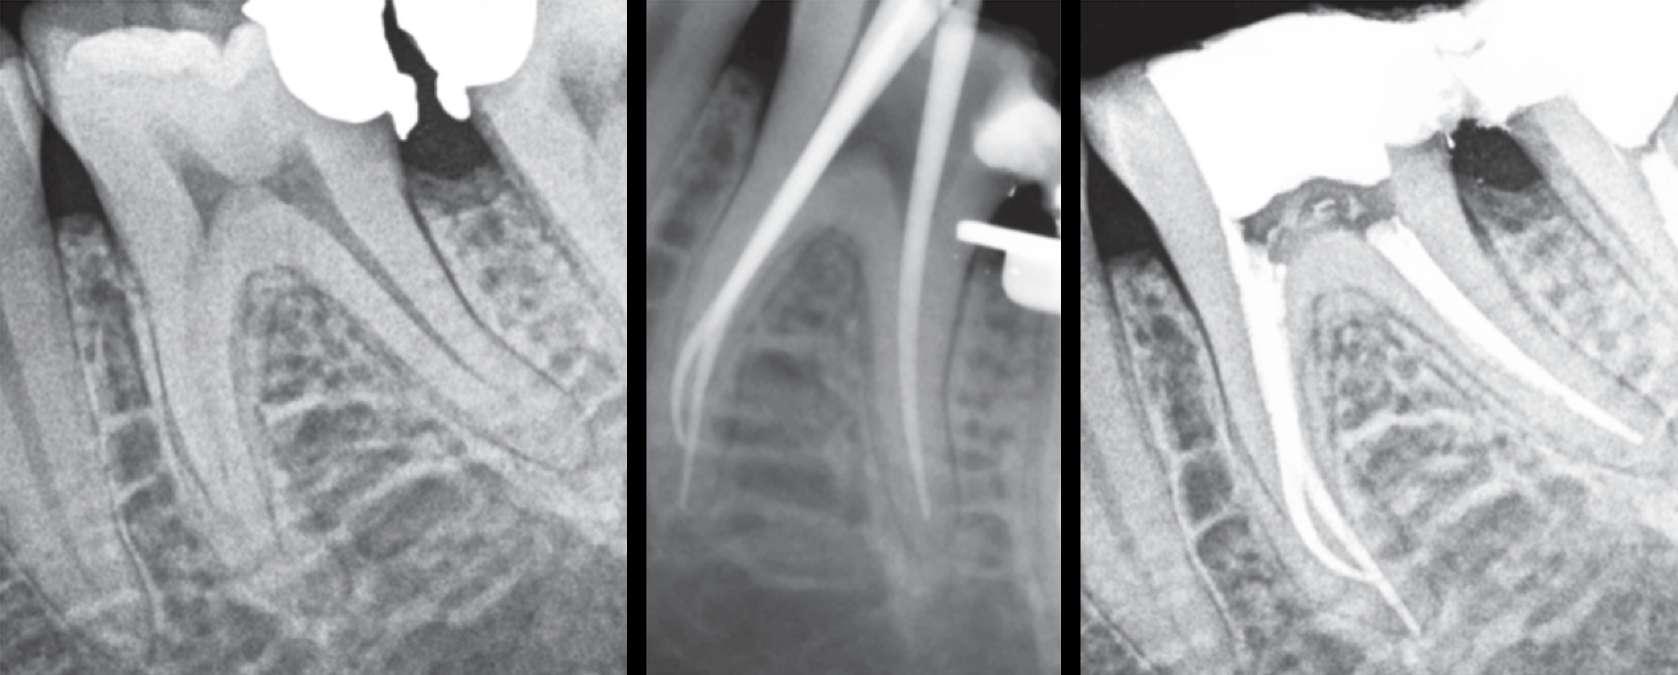

Röntgenologischer Befund: Therapie

Das präoperativ angefertigte diagnostische Röntgenbild zeigt eine insuffiziente Amalgamfüllung im distalen Approximalraum. Die mesiale Wurzel weist eine periapikale Osteolyse auf (Abbildung 1).

Gleitpfad rotierend mit EdgeFile X7 der Größe 17.04 und 25.04 erweitert und final bis auf 30.04 aufbereitet (Abbildung 2).

Abbildung 1: Präoperative Diagnostische Aufnahme

Abbildung 2: Blick auf das mesiale Kanalsystem nach Präparation

Abbildung 3: Ansicht nach Obturation Abbildung 4: Masterpointaufnahme Abbildung 5: Nach Wurzelfüllung und adhäsivem Verschluss

Röntgenologischer Befund: Zahn 27 weist eine apikale Aufhellung im Sinne einer chronischen apikalen Parodontitis auf (Abbildung 6).

Abbildung 6: Präoperative diagnostische Aufnahme

Zur koronalen Erweiterung der Kanäle wurde eine EdgeFile X7 der Größe 17.06 eingesetzt. Die Erstellung des Gleitpfads konnte rein mechanisch durchgeführt werden. Hierzu wurden EdgeFile X7 der Größe 17.04, 17.06 in alternierender Weise bis zum Erreichen der näherungsweise röntgenologisch bestimmten vorläufigen Arbeitslänge eingesetzt. Nach elektrometrischer Bestimmung der Arbeitslänge mit C-Pilot Feilen der Größe 8 und 10 erfolgte die weitere Präparation mit EdgeFile X7 der Größe 20.06, 25.06 und 30.06. Die Kanäle wurden nach der finalen Aufbereitung für 60 Sekunden mit 17% EDTA gespült. Die Abschlussspülung erfolgte schallaktiviert mit 6% NaOCl. Eine Masterpointaufnahme diente zur Verifizierung der Aufbereitung und der Passung der angepassten Guttaperchaspitzen (Abbildung 7). Nach Trocknung mit Mikroabsaugung und Papierspitzen wurden alle Kanäle in warm vertikaler Fülltechnik mit biokeramischem Sealer obturiert (Abbildung 8). Der adhäsive Verschluss erfolgte mit Bulk Fill Flow Komposit (Abbildung 9).

Abbildung 7: Masterpointaufnahme

Abbildung 8: Kontrollaufnahme nach Wurzelfüllung

Abbildung 9: Kontrollaufnahme nach adhäsivem Verschluss

Röntgenologischer Befund:

Das präoperativ angefertigte Röntgenbild (Abbildung 10) zeigt den bereits vom Vorbehandler trepanierten Zahn 27. Die Wurzelfüllung erscheint inhomogen. Das Wurzelfüllmaterial im mesiobukkalen Kanal ist über den röntgenologischen Apex hinaus extendiert und es zeigt sich eine periapikale Osteolyse der mesiobukkalen Wurzel.

Abbildung 10: Präoperative diagnostische Aufnahme

Die Revisionsbehandlung erfolgte in zwei Sitzungen. Nach Anlegen des Kofferdams wurde die provisorische Füllung entfernt und die Zugangskavität gereinigt. Im Anschluss erfolgte die intrakoronale Diagnostik (Abbildung 11). Es zeigte sich bakteriell besiedeltes Wurzelfüllmaterial im mesiobukkalen, distobukkalen und palatinalen Kanal. Das Orifizium des mesiobukkalen Kanals war in palatinaler Richtung erweitert. Die Entfernung eines mesialen Dentinüberhangs mit langschaftigen Rosenbohrern legte das weit nach palatinal verlagerte Orifizium des zweiten mesiobukkalen Kanals frei. Die Entfernung des Wurzelfüllmaterials erfolgte mithilfe von EdgeFile X7 der Größe 25.06, und 17.06 in Crown Down Technik um die Verschleppung von Keimen und bakteriell besiedeltem Wurzelfüllmaterial nach apikal zu reduzieren. Die Erschließung und initiale Aufbereitung des zweiten mesiobukkalen Kanals wurde mithilfe der EdgeFile X7 der Größe 17.04, 17.06 in alternierender Weise wie oben beschrieben durchgeführt. Nach elektrometrischer Bestimmung der Arbeitslänge aller Kanäle wurde die Präparation mit EdgeFile X7 auf voller Arbeitslänge fortgesetzt. Im ersten mesiobukkalen Kanal, distobukkal und palatinal wurde die Aufbereitung mit EdgeFile X7 der Größe 40.06 abgeschlossen, während der zweite mesiobukkal Kanal bis 30.06 aufbereitet wurde (Abbildung 13).

Abbildung 11: Nach Ausarbeiten der primären Zugangskavität; Darstellung des mb2 in der Nähe des palatinalen Kanals

Nach Abschluss der Präparation wurden die Kanäle getrocknet, Kalziumhydroxid auf volle Arbeitslänge eingebracht und der Zahn provisorisch mit einer adhäsiven Kompositfüllung verschlossen. Die Weiterbehandlung fand nach zwei Wochen bei Beschwerdefreiheit statt. Nach erneuter elektrometrischer Kontrolle der Arbeitslänge, Anfertigung einer Masterpointaufnahme (Abbildung 12) und schallaktivierter Abschlussspülung mit 17% EDTA und 6% NaOCl wurden die Kanäle in warm vertikaler Fülltechnik mit biokeramischem Sealer gefüllt (Abbildung 15). Der direkte adhäsive Verschluss der Zugang erfolgte mit einem Bulk Fill Flow Komposit (Abbildung 14).

Abbildung 12: Masterpointaufnahme

Abbildung 13: Kanalsystem nach Aufbereitung

Abbildung 14: Nach Obturation und adhäsivem Verschluss Abbildung 15: Zugangskavität nach Obturation